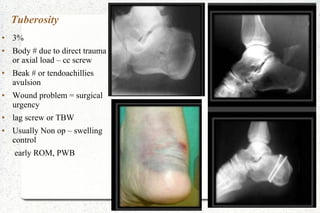

Tuberosity

● 3%

● Body # due to direct trauma

or axial load – cc screw

● Beak # or tendoachillies

avulsion

● Wound problem = surgical

urgency

● lag screw or TBW

● Usually Non op – swelling

control

early ROM, PWB